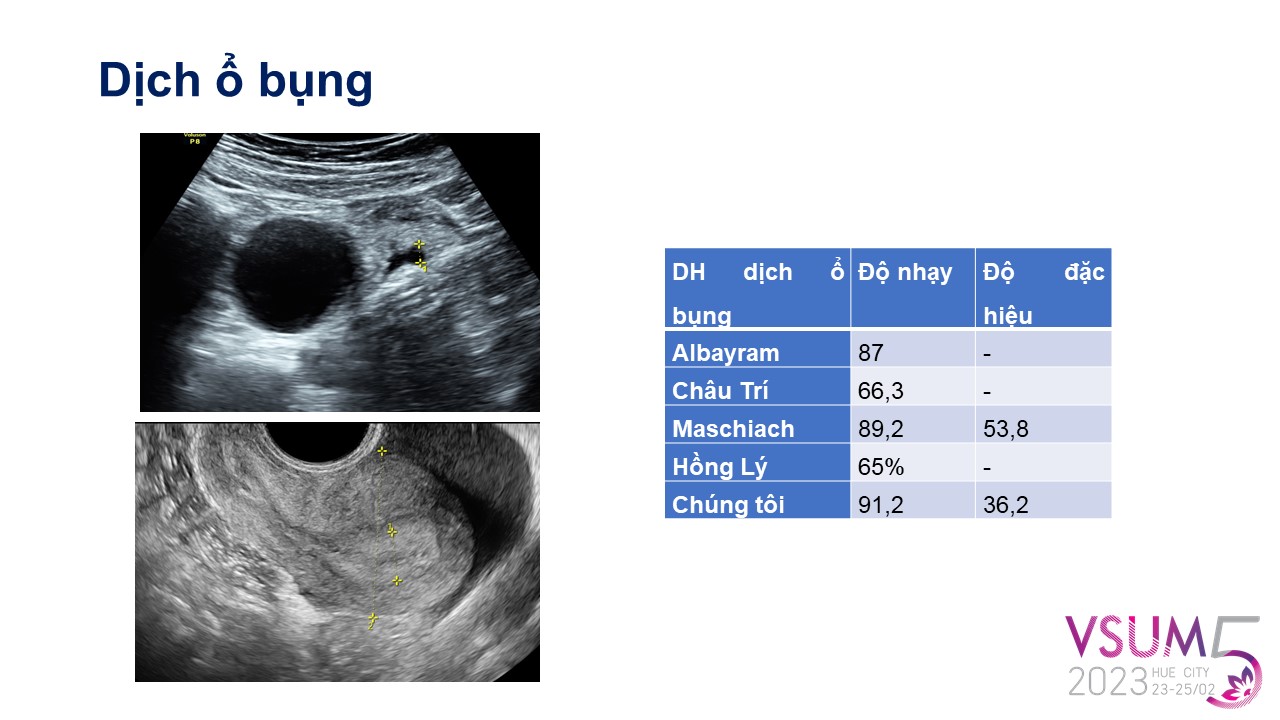

Giá trị của siêu âm ngả âm đạo trong đánh giá xoắn phần phụ